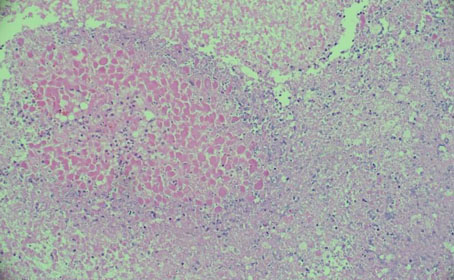

The histological characteristic of OAC is the presence of large polygonal cells with abundant eosinophilic cytoplasm, as a result of mitochondrial accumulation [3]. The diagnostic criteria used for ACC, the Weiss system, overestimates malignant potential in oncocytic tumors, therefore a separate classification system called the Lin–Weiss–Bisceglia (LWB) classification is used for oncocytic tumors [5],[8]. The LWB system divides oncocytic adrenocortical neoplasms (OANs) into benign, borderline, and malignant categories based on three main criteria: a mitotic rate greater than 5 per 50 high-power fields, vascular invasion, and metastasis. Malignancy is diagnosed if any of these criteria are present, while borderline tumors show only minor criteria, such as a tumor size greater than 10 cm, necrosis, or capsular invasion. This classification system has enhanced the ability to differentiate between benign oncocytic adenomas and OACs. In our patient, the resected specimen showed a well-circumscribed tumor weighing 5458 g, and measuring 26.0 × 25.0 × 16.0 cm. The tumor also had extensive hemorrhage and necrosis, along with a central fibrous scar [9]. Microscopically the patient’s tumor matched the classic histological findings for OAC and exhibited a low Ki-67 index of 2% suggesting a low proliferative rate. However, the tumor did exhibit vascular (renal vein) and capsular invasion (Figure 3, Figure 4, Figure 5, Figure 6). Based on the LWB criteria, malignancy was established due to the vascular invasion. Next-generation-sequencing (NGS) showed TP53 pathway alterations. The malignancy had a low tumor mutation burden and was found to be microsatellite stable. These findings are consistent with recent research suggesting a distinct mitochondrial metabolic profile with an oncocytic variant of ACC [4].

Figure 3: Sheets of tumor cells marked with atypia (H&E×20).

Figure 5: Tumor necrosis H&E×20.